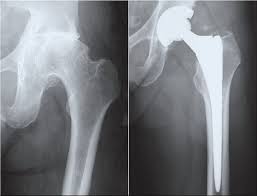

The company ORTHOPEDIC NIKIFOROV was founded in 1998 by the candidate of medical sciences. doctor of orthopedic-traumatologist of the highest category Nikiforov IA Owing to high professionalism and results of work, ORTONIC has gained well-deserved reputation and reputation among colleagues and population of Dnepropetrovsk region and CIS countries (Russia, Moldova, Armenia, etc.). The principle of the enterprise is NO IMPOSSIBLE, it is based on knowledge, experience and active implementation of modern technologies in orthopedics and traumatology. Conservative methods of treatment include individual selection of medicines, therapeutic blockades, manual therapy, massage, physiotherapy (vibration table, magnetotherapy, bioptron, electromyostimulation, etc.), rehabilitation with the suggestion of the necessary concomitant devices and means for the fastest recovery (corsets, bandages, various joint fixators, crutches, walking sticks, etc.). Various minor invasive interventions (chymonucleolysis, vertebroplasty, kyphoplasty, percutaneous nucleoplasty using cold plasma) that are performed on an outpatient basis are successfully used to treat problems associated with spine pathology. The latest modern treatment methods introduced in our company are endoscopic operations using the TYSSES technique of Joimax (Germany) with intervertebral hernias, stenosis and other pathologies of the spine, which allow to avoid complications occurring during open operations and the accompanying general anesthesia. We have many years of successful experience in traditional and modern minimally invasive endoprosthetics of large and small joints, which remains the main direction of our activity. Our company is the exclusive representative of the German company IO International Orthopaedics Holding GmbH, which based on the already known prostheses, its ideas and technological capabilities, has developed and implemented a new concept in hip replacement - an artificial joint prosthesis (ICON). We assist interested colleagues in training the operative technique for installing an artificial joint prosthesis - ICON, both in the workplace and in Germany. For 20 years we have been successfully cooperating with Sanitatshaus Gerd Klinz ortho team, an enterprise that for 20 years has been one of the leading places in Germany for the production of functional prostheses of the upper and lower limbs, as well as cosmetic prostheses of limbs and other body parts (nose, ears, eyeballs, fingers). We have an atmosphere of friendliness and human participation. Politeness, benevolence, the desire to understand and help is the basis of our attitude towards patients. We are always glad to see you and will do our best to make you feel great! We are waiting for you at: Ukraine, Dnepr, Gagarin Ave., 13 (under reconstruction) on all questions to address: tel .: +38 (050) 488-88-92 E-mail: orthonik.ukr@gmail.com Germany, Spine Nano Klinik, Zeppelinstr. 21, Potsdam Tel. +4901801121919 E-mail: kmw.nikiforov@hotmail.de